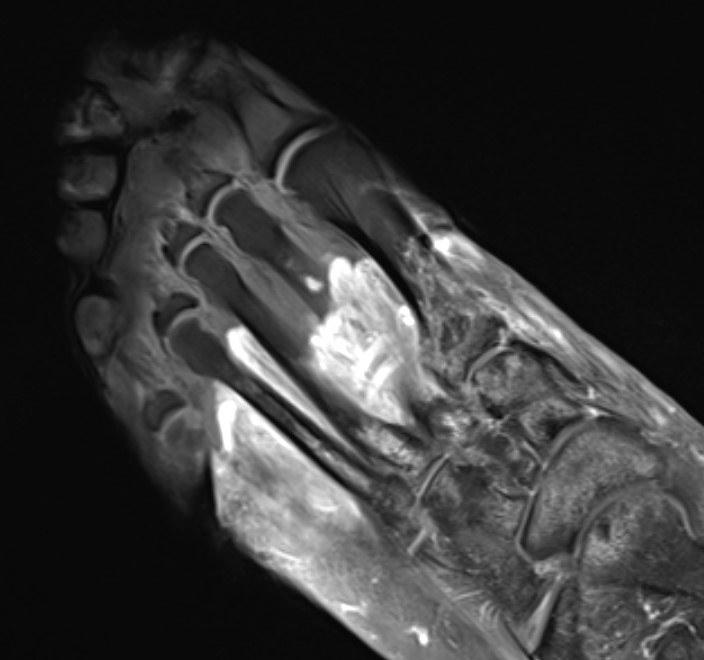

U większości pacjentów chorujących na Covid-19 bóle mięśni i stawów szybko mijają. Jest jednak grupa chorych, u których objawy na przykład reumatoidalnego zapalenia stawów, czy zapalenia mięśni są bardziej poważne i utrzymują się dłużej. Naukowcy z Northwestern Medicine po raz pierwszy potwierdzili te objawy z pomocą obrazów wykonanych techniką magnetycznego rezonansu jądrowego (NMR). W swojej publikacji opisują przypadki pacjentów hospitalizowanych w Northwestern Memorial Hospital z powodu Covid-19 w okresie od maja do grudnia 2020 roku.

Przekonaliśmy się, że Covid-19 może sprowokować reakcję oganizmu przeciwko sobie na różne sposoby, w tym prowadzący do reumatoidalnego zapalenia stawów, które potem będzie wymagało już ciągłej terapii - mówi współautorka pracy, radiolog, dr Swati Deshmukh. U wielu pacjentów objawy kostno-szkieletowe ustępują, ale są tacy, u których są poważniejsze i prowadzą do poważnego pogorszenia jakości życia. Nowoczesne metody obrazowania pokazują nam, czy bóle stawów i mięśni są podobne do tych, które odczuwamy w grypie, czy stoi za nimi znacznie bardziej podstępny mechanizm.

Naukowcy z Northwestern Medicine zwracają uwagę na to, że nowoczesne metody diagnostyczne, w tym obrazowanie z pomocą Magnetycznego Rezonansu Jądrowego, tomografia komputerowa, czy ultrasonografia mogą pomóc zdiagnozować długotrwałe objawy Covid-19 nawet u osób, które wcześniej nie wiedziały, że przeszły zakażenie koronawirusem. To przyspieszy zastosowanie terapii, które mogą te objawy złagodzić. Taka diagnostyka, wykazująca obecność stanów zapalnych, obrzęków, czy nawet obszarów martwicy może też pomóc w ocenie, czy do uszkodzenia doszło w wyniku bezpośredniego działanie wirusa, czy w rezultacie sprowokowanej przez niego odpowiedzi autoimmunologicznej.